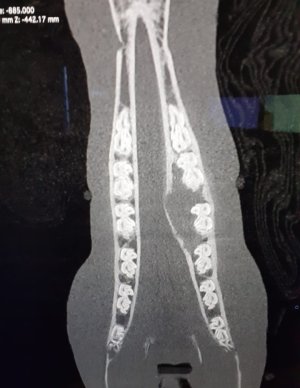

From a other thread I realised I have so many funky images on by phone of various xrays and tendon scans etc. So the ones with no names visible I will pop up here one at a time for you to figure out what's wrong.

We will start off with an easy one - tell me what you think the problem is and then give me the solution:

• Screenshot_20230724-164847_Gallery.jpg

Screenshot_20230724-164847_Gallery.jpg

204.7 KB · Views: 401